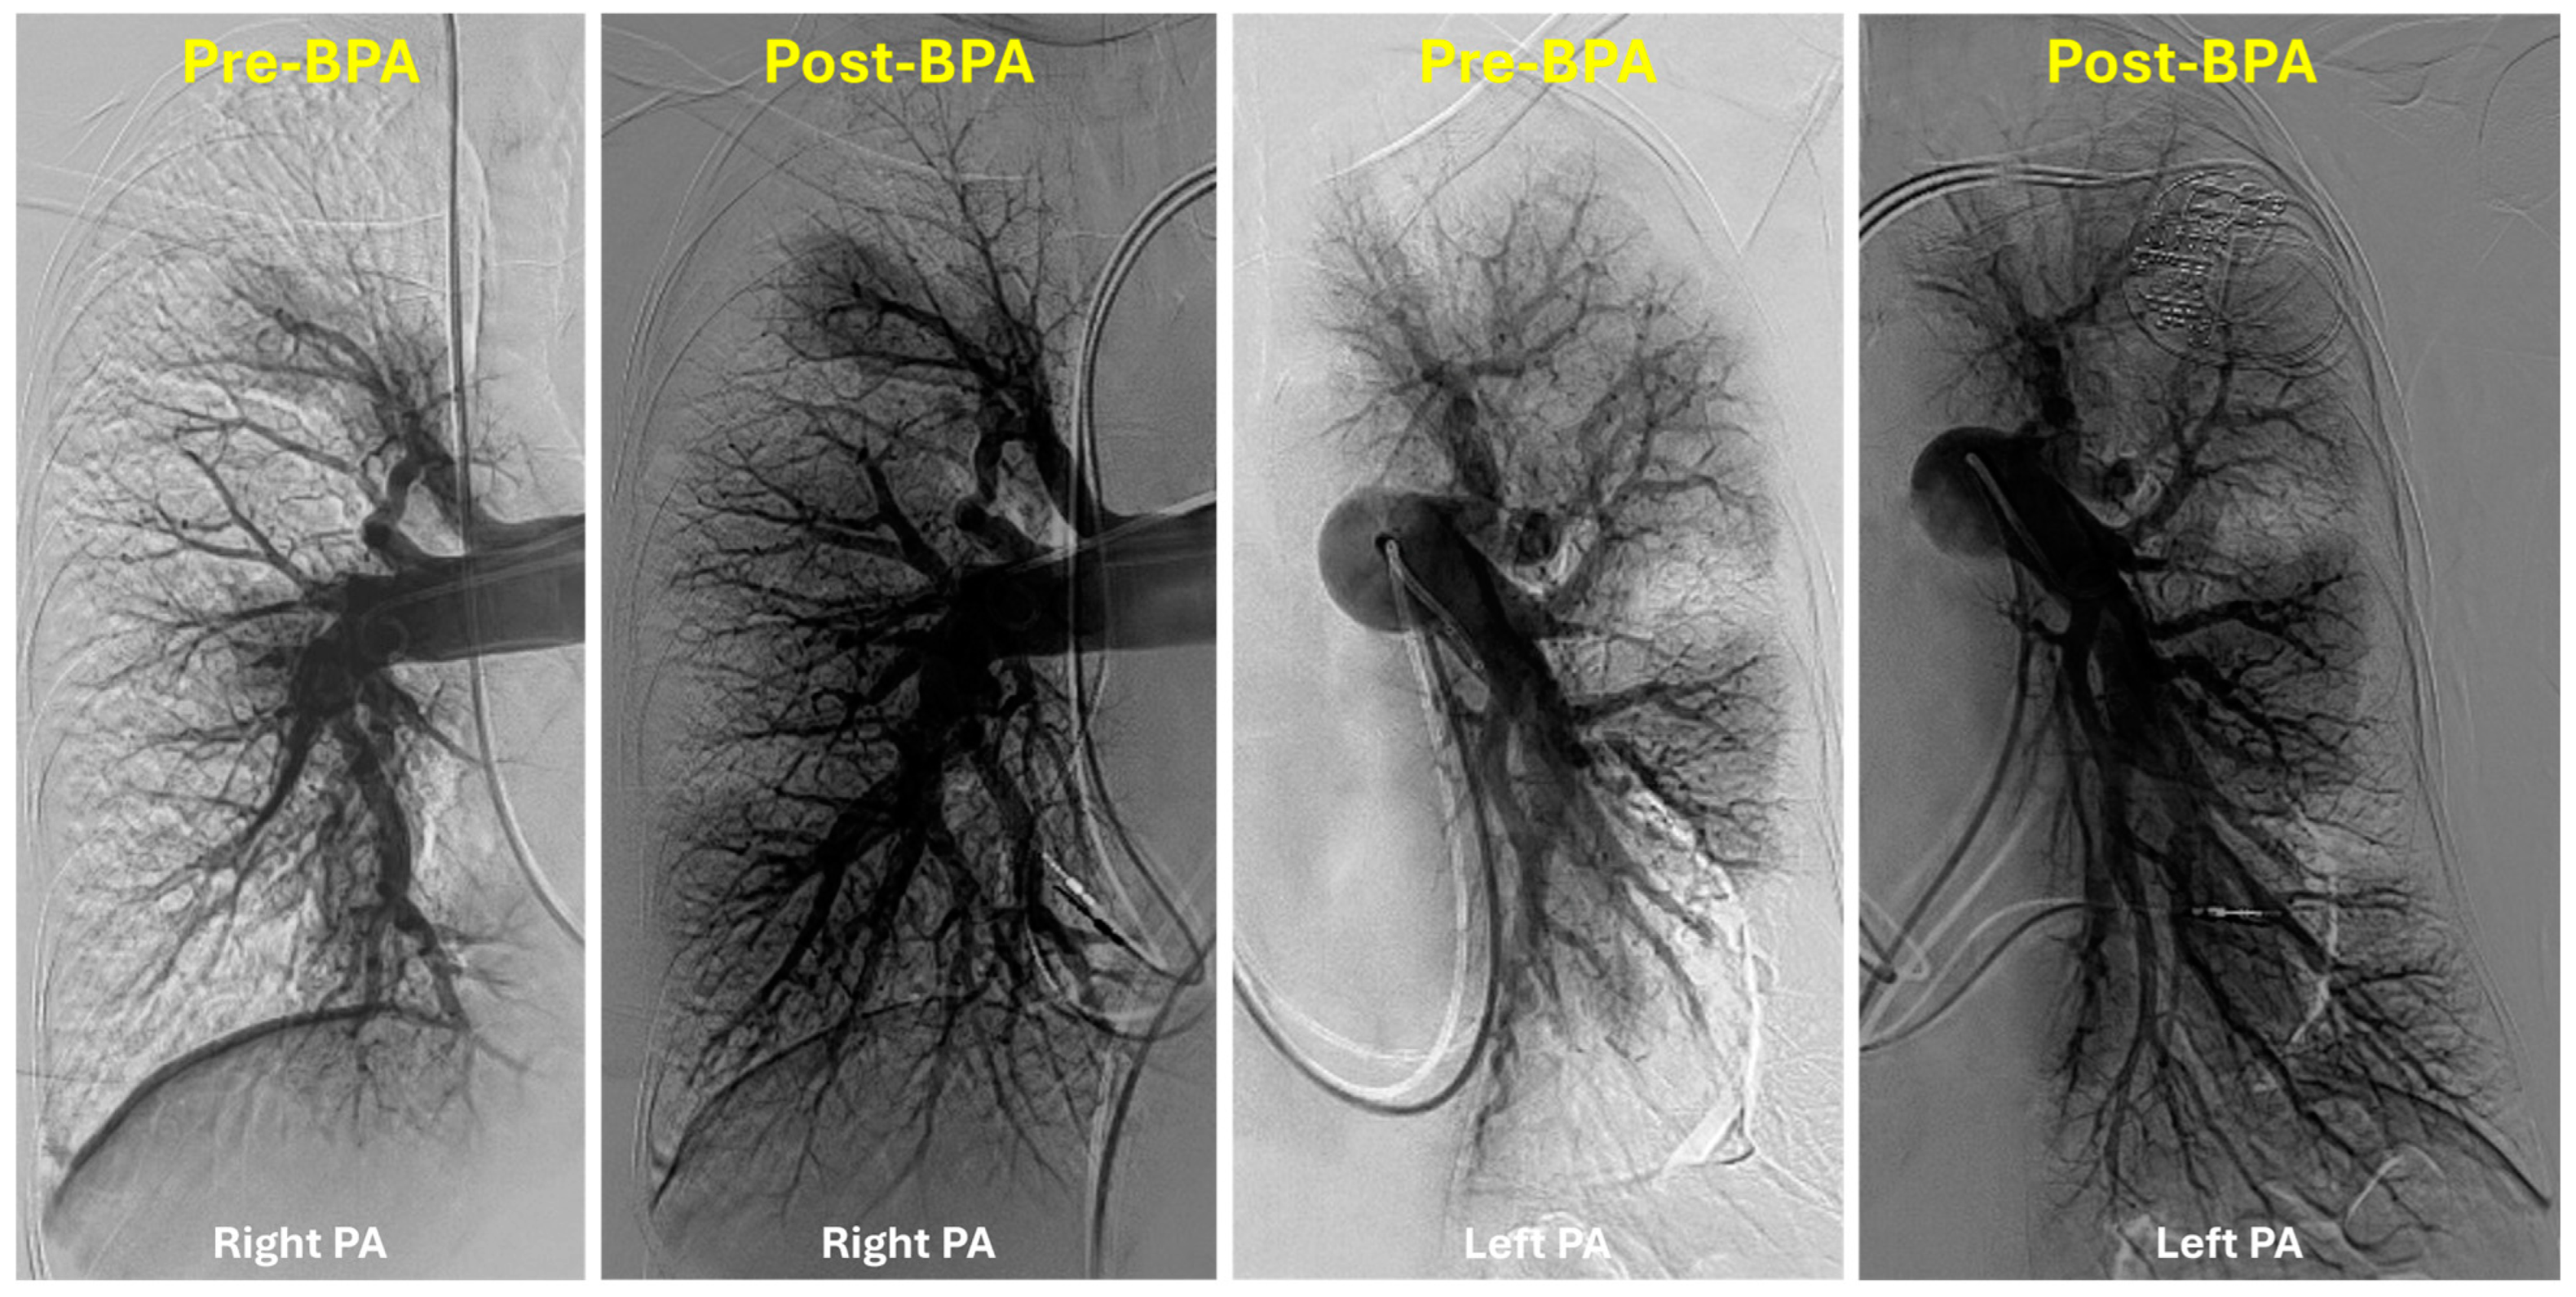

5. Technical Considerations

6. Outcomes